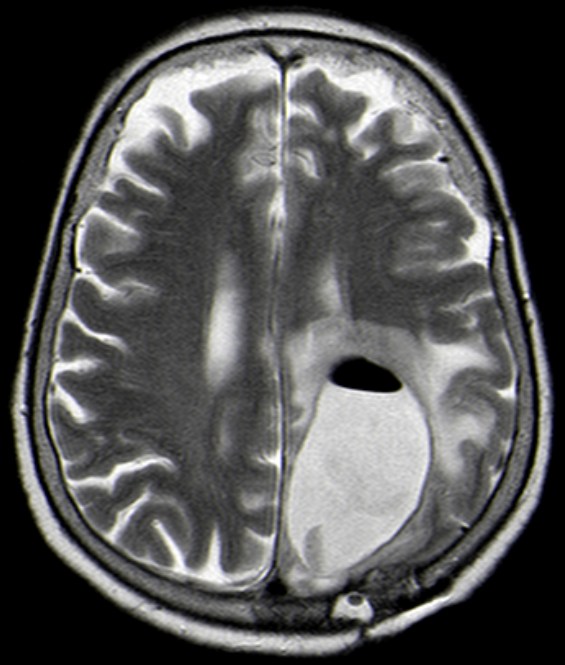

Je vollständiger ein Glioblastom entfernt wird, um so höher ist die Überlebensrate (5). | Einbringung von Gliadel | 66-jährige Frau mit Progredienz nach anoperiertem Glioblastom. Reoperation bei zunehmender Eintrübung. Jetzt Hirnabszess.![]() | ||||||||||||||||||||||||||||||||||||||||||||||||||||||||